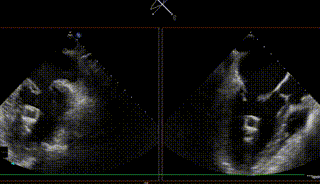

【二尖瓣相关参数】二尖瓣关闭时P2P3呈弓形脱入左房。二尖瓣后叶脱垂并重度偏心性反流(原发性:Carpentier II型,缩流颈8.3mm,反流面积0.42cm²,反流容积71ml);P2+P3区脱垂,脱垂范围约14×10mm,前叶2偏3区瓣体长度:25mm,后叶2偏3区瓣体长度:19mm;MVA:6.33cm²。左房内径47mm,左室60/39mm。

图1-4. 术前在交界、左室长轴切面及3D视角下可见大量二尖瓣反流,反流区宽,MultiVue下可见P2-P3脱垂

图5-7. 顶心尖确定穿刺点,跨瓣球跨瓣及寻找A-P、1-3区方向维度